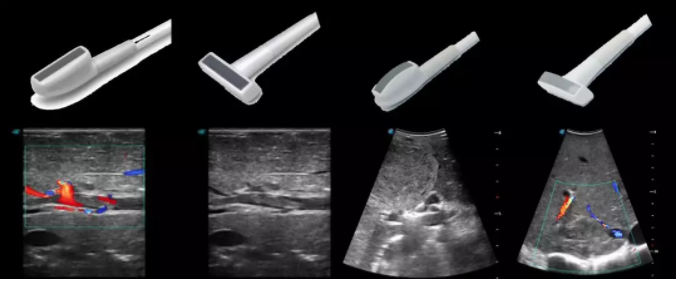

線陣/凸陣不同選擇,多種外形設(shè)計(jì)可以滿足適用于不同的臨床科室,滿足不同醫(yī)生的使用需求;

輕便小巧,方便持握;

防水、易消毒;

應(yīng)用科室:手術(shù)室、肝膽外科、消化外科、腫瘤科、心胸外科、泌尿外科、婦產(chǎn)科等